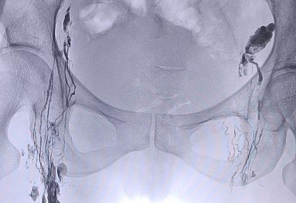

李女士于外院行宫颈手术后每日盆腔引流液约600ml,持续1月余,辗转于西安多个医院,治疗效果欠佳。后入住东院肿瘤外科。行盆腔淋巴管显影,术中明确定位淋巴漏位置,并行淋巴管栓塞。术后很快引流液量降低至正常范围。